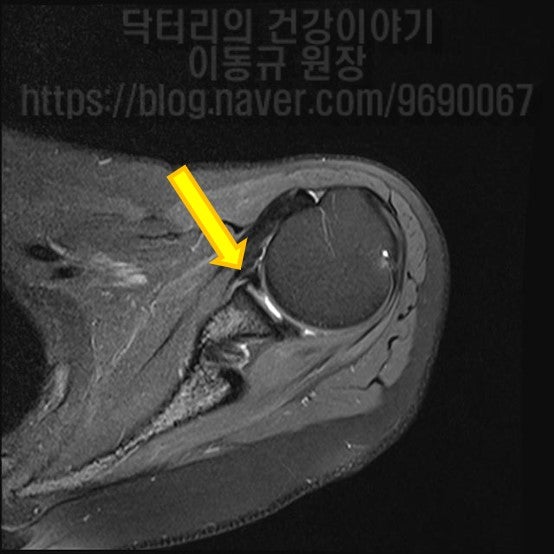

MRI 를 살펴보도록 하겠습니다.

MRI 에서 노란색 화살표로 표시된 부위가 전방관절와순 부위인데 좌측 MRI 에서는 골막까지 떨어진 모습이 보이고 우측 MRI 에서는 관절와순이 파열된 모습이 보입니다.

종합적으로 판단했을때 이학적 검사상 전방불안정성이 보이며 MRI 상 전방 관절와순 파열이 관찰되었습니다. 진단은 어깨 탈구로 인한 전방 관절와순 파열 이며 이에 대해 수술적 치료를 하였습니다.